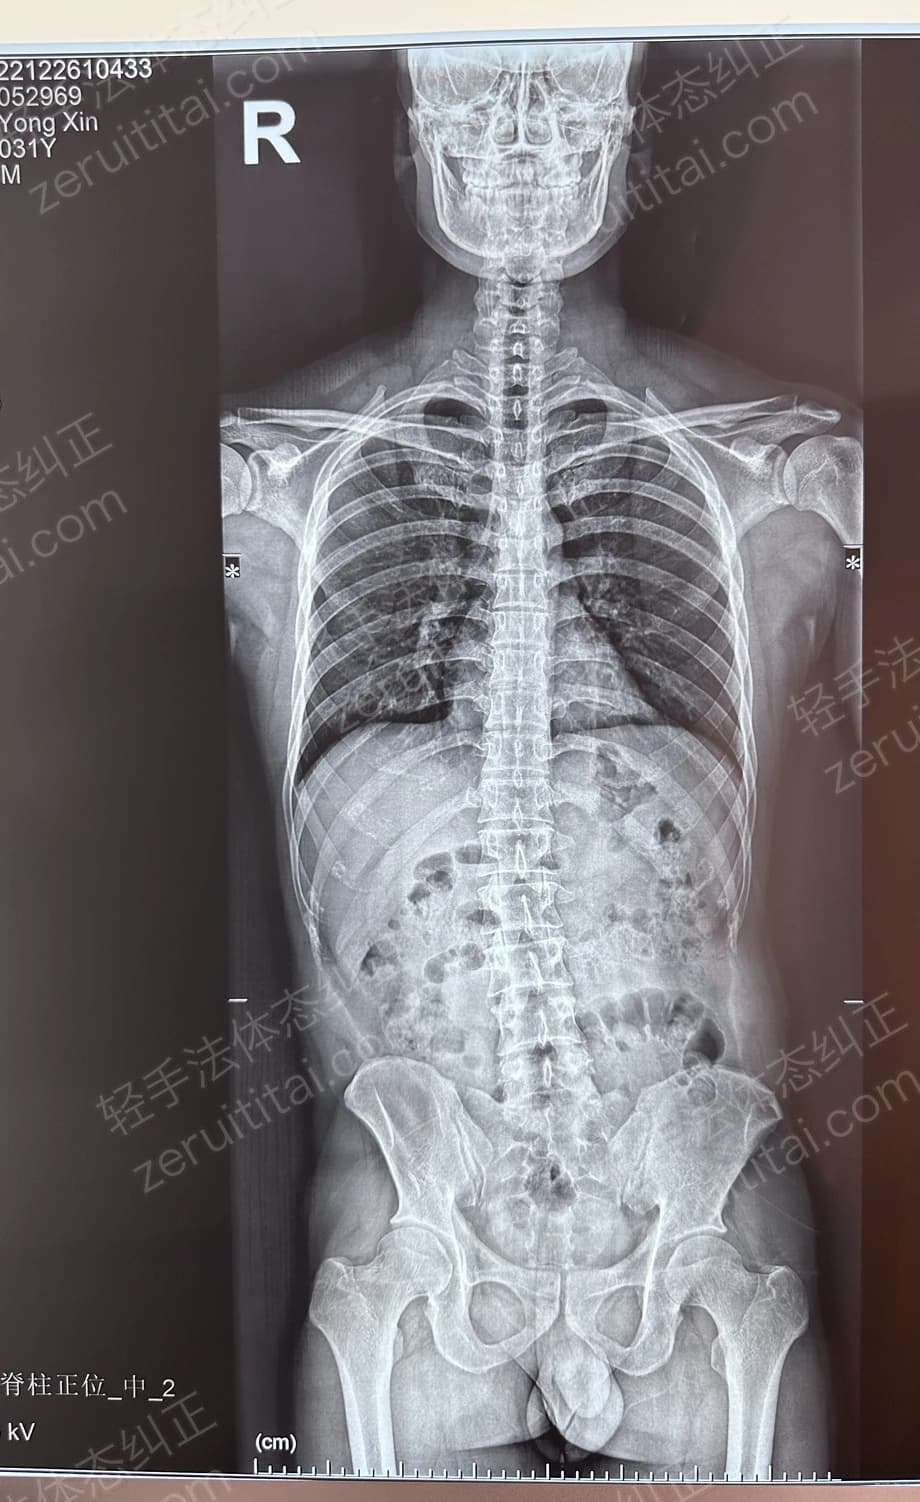

2023.12.16

第 5 次记录